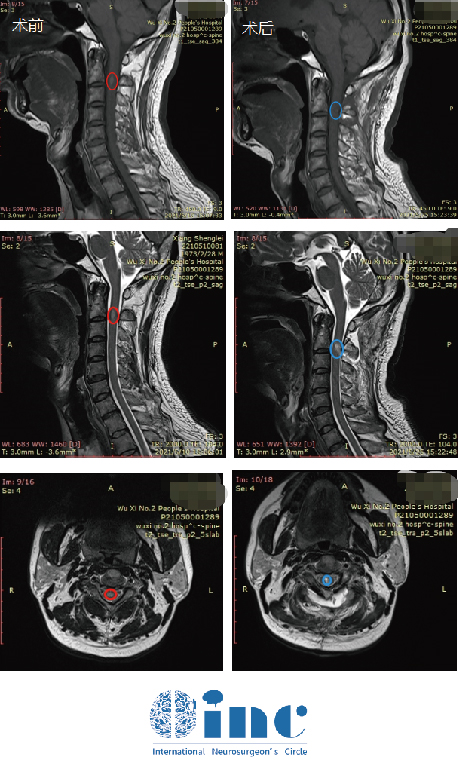

术前颈2平面脊髓内可见椭圆形短T1长T2信号,信号较均匀,边界尚清,大小约7.8X4.1X5.0mm,增强后明显强化。术后肿瘤得到顺利全切,无新发神经损伤,无瘫痪,术后复查没有复发

接受手术的刘先生麻醉复苏后查体无神经功能缺损,当天就拔除气管插管,术后2天即转出了ICU,术后3天可下地自如行走。术后两周出院,患者术前症症状明显好转,无术后感染或并发症,无需其他辅助治疗。

刘先生的术前术后MRI对比

刘先生的术后病理结果为良性,无需其他治疗